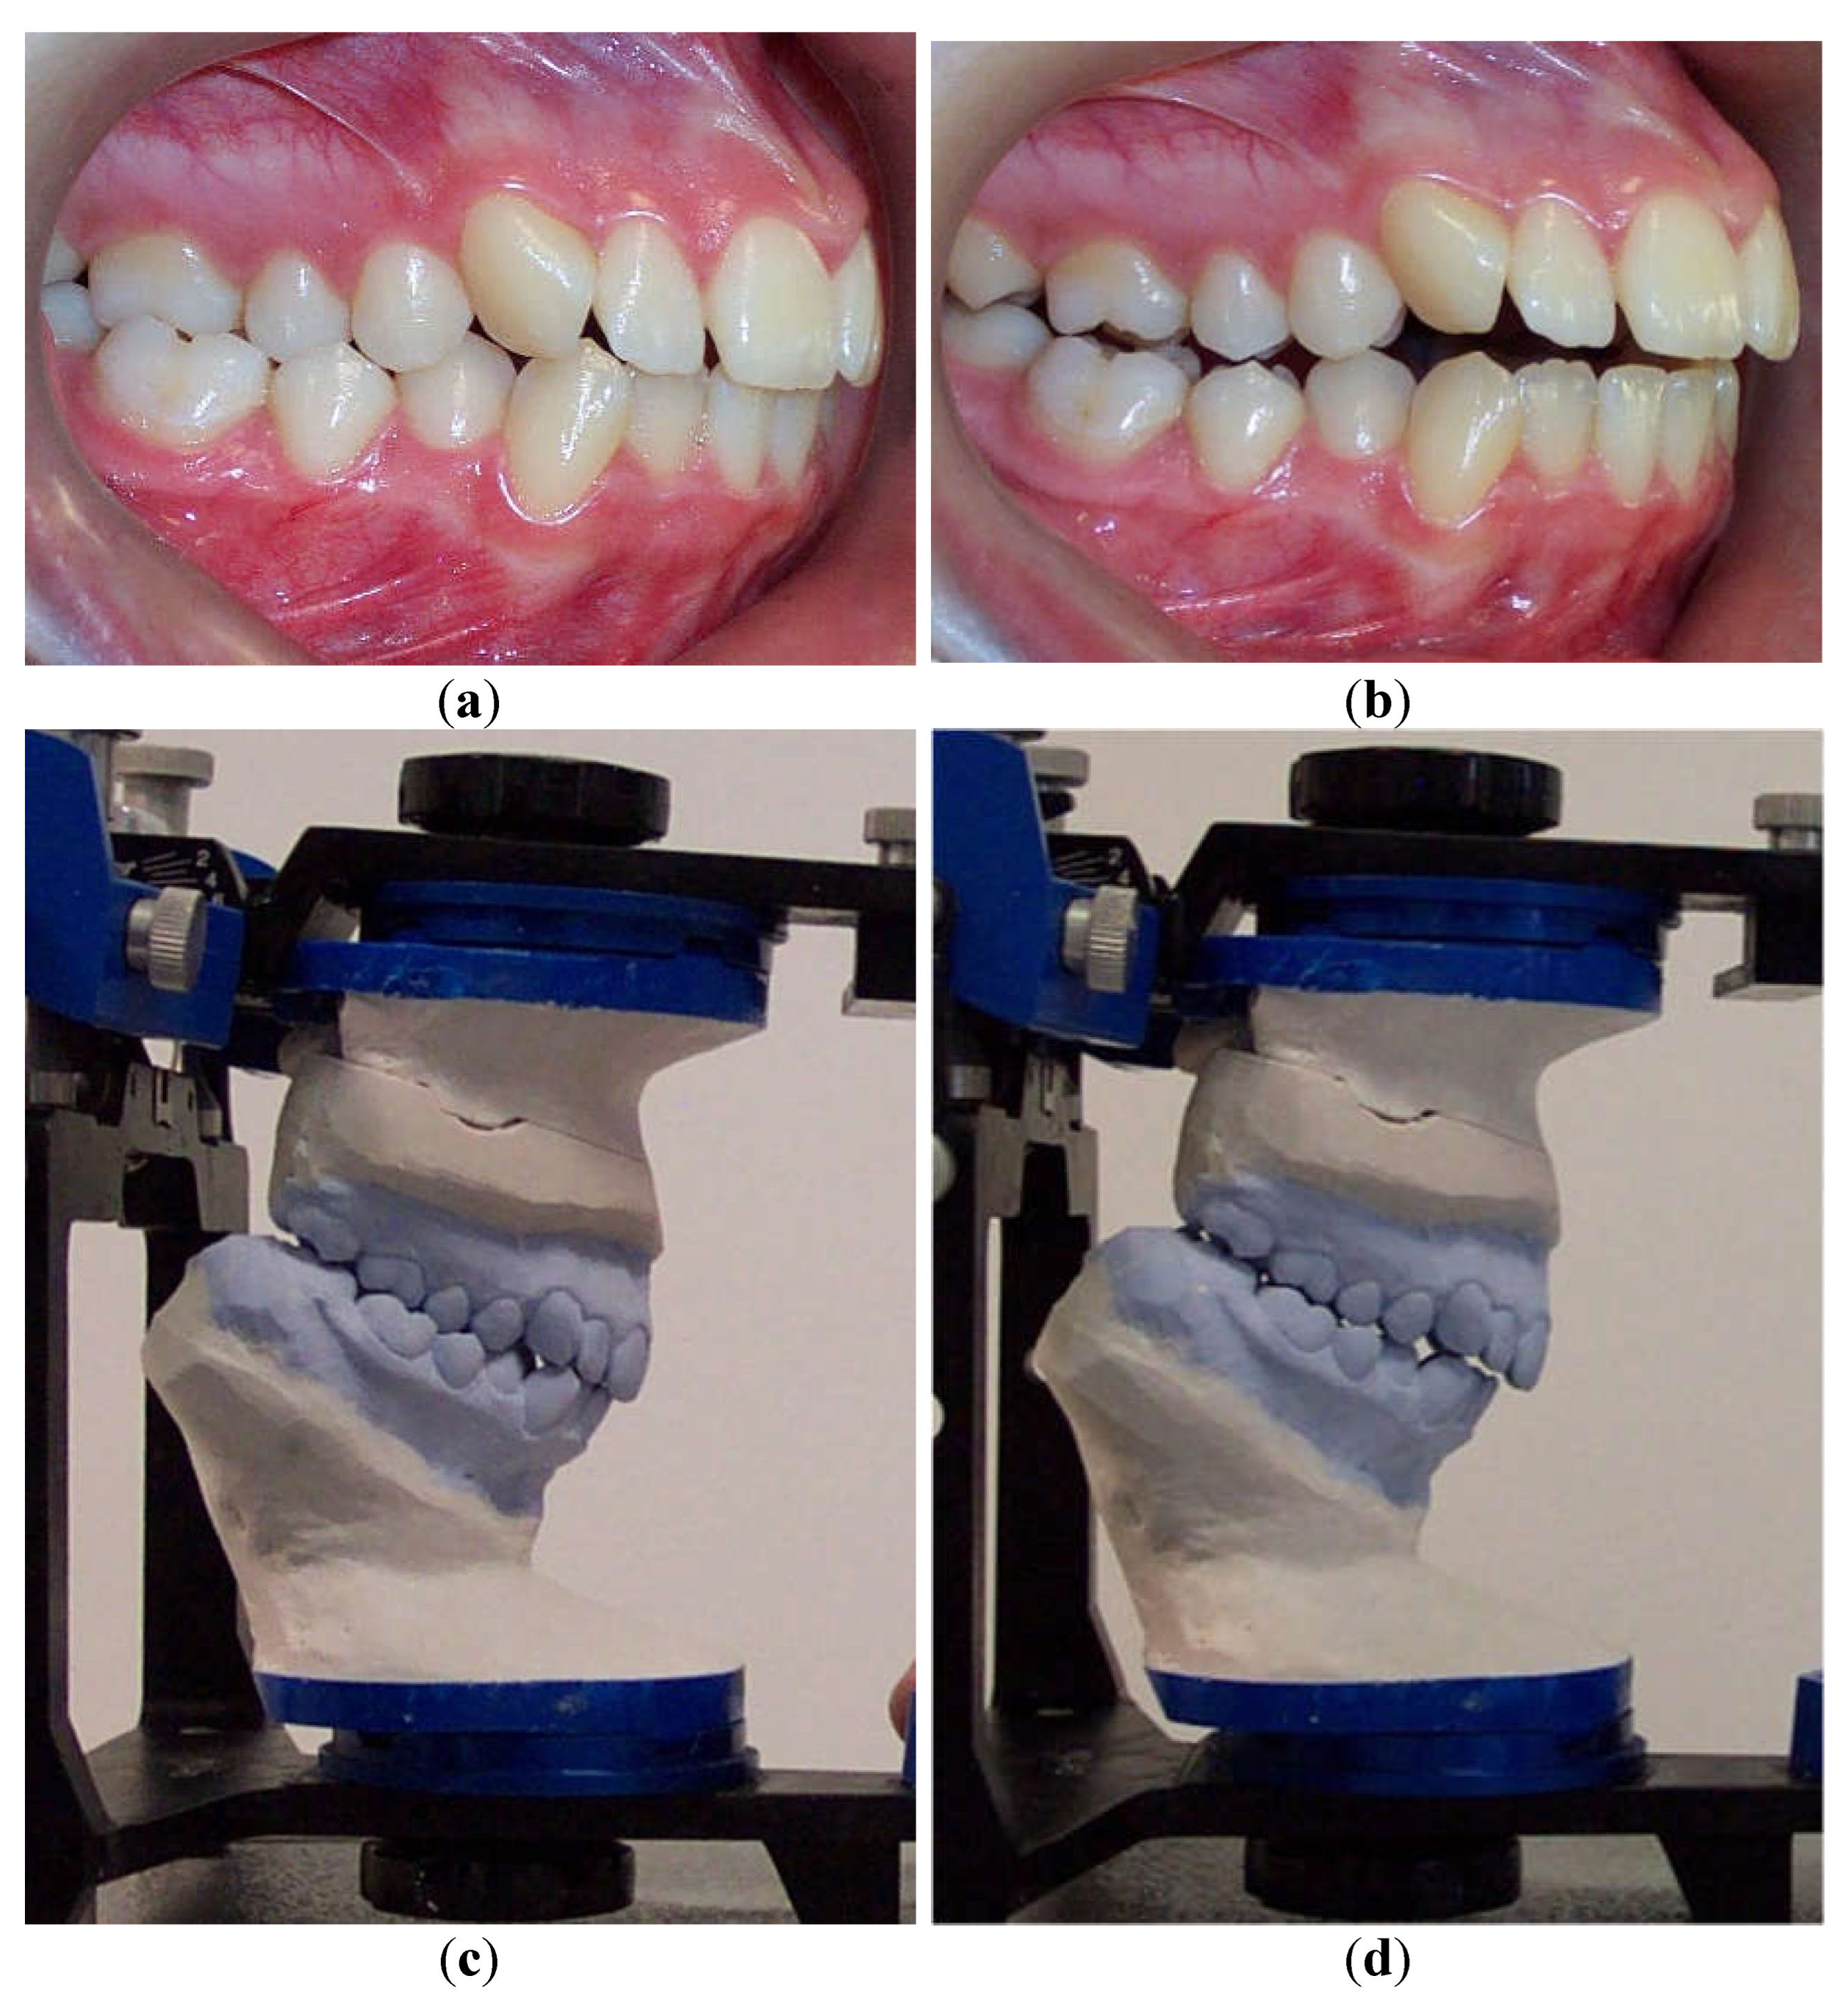

To accurately evaluate the effect of interarch relationship changes on dentofacial characteristics, cephalometric analysis of lateral cephalograms was performed before and after the splint therapy (Figure 6).

Figure 6. Comparison of pre- and post-splint cephalograms. (a) Cephalometric analysis of pre-splint lateral cephalogram. (b) Cephalometric analysis of post-splint lateral cephalogram. Comparison of pre- and post-splint cephalograms revealed significantly greater mean values of ANB angle (p = 0.007) and Wits appraisal (p = 0.022) after splint therapy than those measured before splint therapy. After splint therapy, a significant increase in mean values was observed for overjet (p = 0.0001) and a decrease for overbite (p = 0.0001) when compared to values obtained before the splint therapy.

The changes in dental interarch relationship characteristics that occur after the splint therapy might alter the type of dental malocclusion and indirectly affect a correct orthodontic diagnosis. To accurately evaluate the impact of interarch relationship changes on facial characteristics and orthodontic diagnostic procedures, an evaluation of cephalometric data was performed. We analyzed differences in cephalometric measurements between the cephalograms traced in the MIP before and in the CR position after the neuromuscular deprogramming and evaluated the eventual changes in dentofacial characteristics. Eight linear and eight angular cephalometric variables were evaluated on pre- and post-lateral cephalograms. After comparison before and after the splint therapy, the results of this study showed statistically significant differences for overjet, overbite, ANB angle, and Wits appraisal variables, in agreement with earlier studies in which authors found differences for similar parameters [20,21,37]. The significantly larger values of ANB, overjet, Wits appraisal, and the smaller value of the overbite variable most substantially contributed to changes in dentofacial characteristics, whereby most subjects acquired a more dolichofacial skeletal pattern and retrognathic position of the mandible in the CR position. Our findings were in close agreement with similar investigations by other authors [20,21,22,23,24,37].